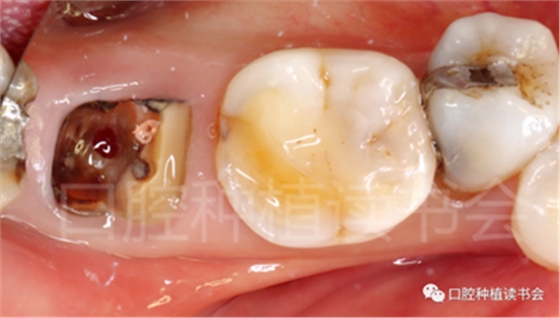

患者為70歲女性,右下后牙樁核冠因遠(yuǎn)中牙根縱裂脫落,全身健康狀況良好,輕度骨質(zhì)疏松??趦?nèi)檢查:47殘根,遠(yuǎn)中根縱裂,部分根面已腐至齦下2mm,叩(++),松(-);48近中傾斜阻生,咬合關(guān)系、修復(fù)間隙及牙周情況正常(圖12)。

圖12 遠(yuǎn)中根縱裂及根面齲導(dǎo)致47殘根無(wú)法保留。

術(shù)前CBCT(美亞光電)檢查:47根分叉下方骨高度及骨寬度滿足即刻種植要求(圖13)。

圖13 47根分叉區(qū)骨寬度及骨高度(與下頜神經(jīng)管之間的距離)滿足即刻種植要求。